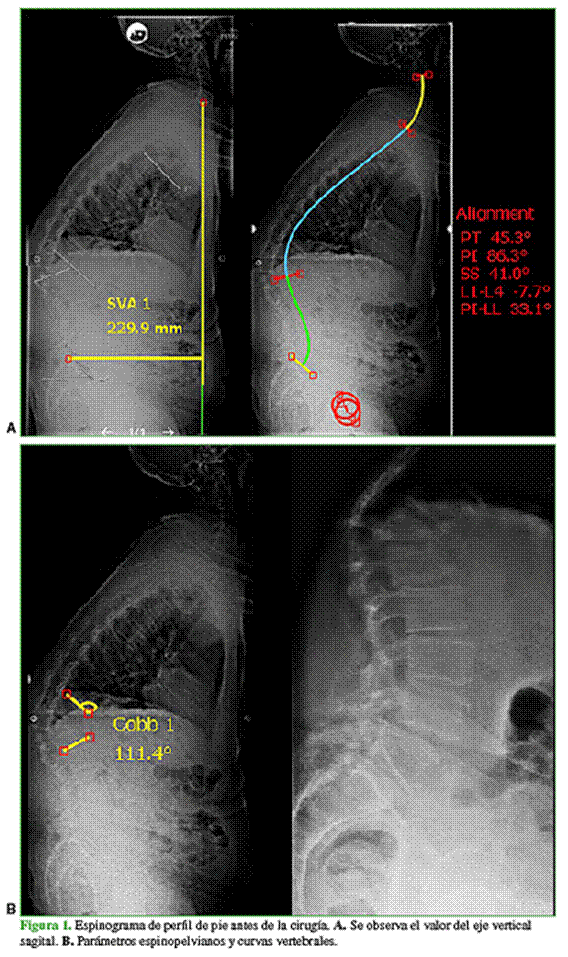

Se solicitaron estudios por imágenes. El espinograma de pie mostró un desequilibrio sagital global. Con el sistema SurgiMap®, se midieron los parámetros espinopélvicos y se obtuvieron los siguientes resultados: eje vertical sagital (sagital vertical axis, SVA) muy positivo de 229 mm, con un ángulo T1-pelvis (T1-pelvis angle, TPA) de 57°, incidencia pélvica (pelvic incidence, PI) 86°, inclinación pélvica (pelvic tilt, PT) 45°, pendiente sacra (sacral slope, SS) 41°, cifosis torácica (thoracic kyphosis, TK) 60°, lordosis lumbar (lumbar lordosis, LL) 53°, PI-LL 33°, GT 66° y gap de 12. El paciente tenía una deformidad de Gibbus a expensas del acuñamiento anterior de T12, con cifosis segmentaria de T11-L1 de 111° (Figura 1).

En las nuevas mediciones con el programa SurgiMap®, en el espinograma de pie, se observa un SVA positivo de 35 mm y una cifosis segmentaria T11-L1 de 11°, con TPA 27°, PI 74°, PT 34°, SS 40°, TK 37°, LL 49°, PI-LL 24°, GT 29° y gap de 8, con mejoría en todos los parámetros espinopélvicos (Figura 5).